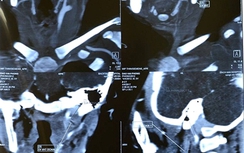

Mới đây, Khoa Hồi sức Cấp cứu, BV Sản Nhi Quảng Ninh tiếp nhận bé gái Nguyễn Ngọc Diễm M. (8 tháng tuổi, trú tại Tp. Uông Bí, tỉnh Quảng Ninh) trong tình trạng trẻ ở nhà xuất hiện sốt cao kèm theo ăn kém, miệng viêm loét từ 3 ngày nay. Được biết thời gian trước đó, ở nhà, cha mẹ đã cho trẻ uống và bôi thuốc cam vào miệng với khoảng 5 thìa cà phê. Sau đó, trẻ ngày càng ăn kém, mệt, viêm loét miệng họng, bỏ bú. Lúc này, gia đình mới đưa trẻ vào bệnh viện thăm khám.

Nghi ngờ cháu bé nhiễm độc chì , các bác sĩ đã chỉ định làm xét nghiệm định lượng chì trong máu. Qua hội chẩn chuyên khoa các bác sĩ chỉ định điều trị tích cực bằng thở máy, an thần, bù nước điện giải, truyền dịch, kháng sinh, vệ sinh họng miệng cho trẻ.

Sau 1 tuần điều trị tích cực, bé M. đã cải thiện đáng kể, tình trạng viêm loét miệng họng đã ổn định, chỉ số xét nghiệm máu cho thấy nồng độ chì đã giảm, các bác sĩ đã cho bé ra viện.